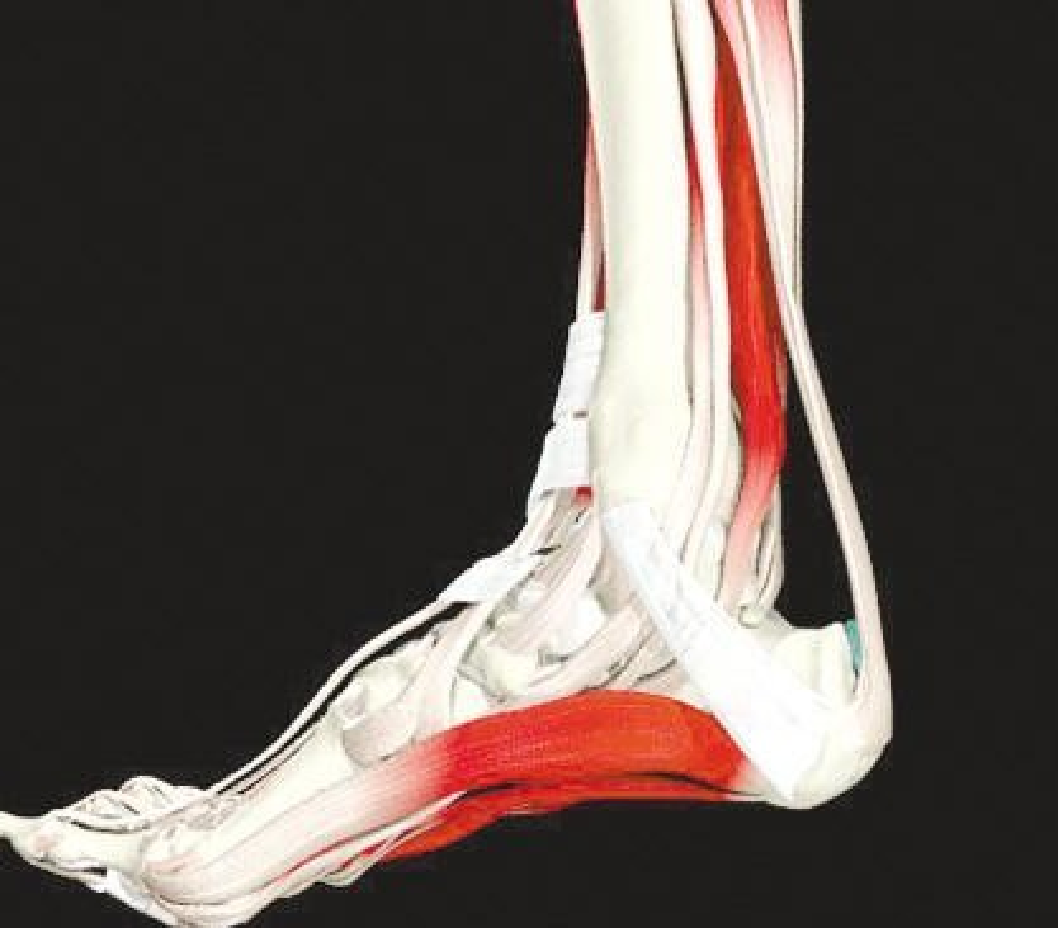

跟腱断裂

病因病理机制:

• 有体育运动史,对抗收缩力的足被动背屈(小腿三头肌群)

• 常位于跟骨上方2~6cm处发生断裂

• 类风湿性关节炎、系统性红斑狼疮、糖尿病和痛风

• 急性断裂:易患因素包括慢性跟腱炎和部分撕裂

MR表现:(信号+形态)

• 正常跟腱呈均匀低信号

• 脂肪抑制T2WI图像上,跟腱内部或跟腱周围软组织出血或水肿表现为信号增高,跟腱断裂/撕裂表现为跟腱连续性中断或波浪状回缩

• 跟腱近端回缩,跟腱边缘磨损,呈螺旋状形态

• 撕裂处增粗的近端与远端之间可见疏松的连接

足底腱膜炎

慢性潜在发展的病变,是引起足跟疼痛的最常见病因。长时间跖屈和足跟部反复轻微创伤导致腱膜的退变和炎症。

最常见的MRI表现:

• 腱膜周围的浅层和深层在T2WI上弥漫性高信号;

• 足底腱膜附着处的跟骨骨髓水肿;

• 在STIR图像上足底腱膜内可见高信号